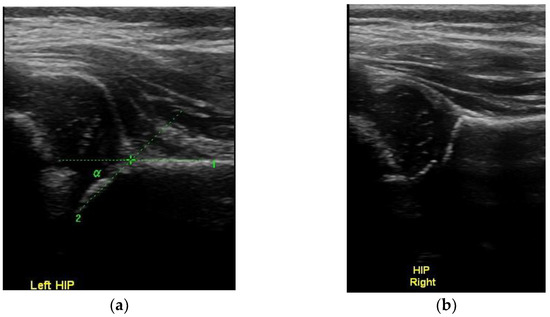

Concentric Circles: A New Ultrasonographic Sign for the Diagnosis of Normal Infantile Hip Development

5. Conclusions